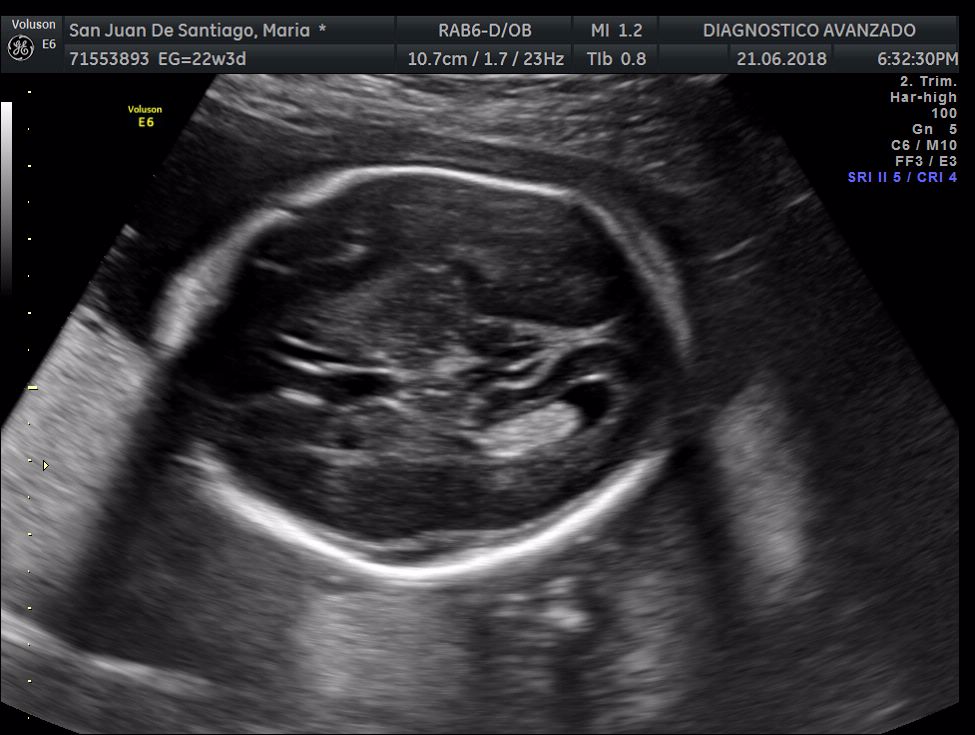

¡Hola a todos! Hoy hemos ido a hacer la tradicional ecografía 3D de la niña, os dejamos todo el material (aunque es un poco demasiado).